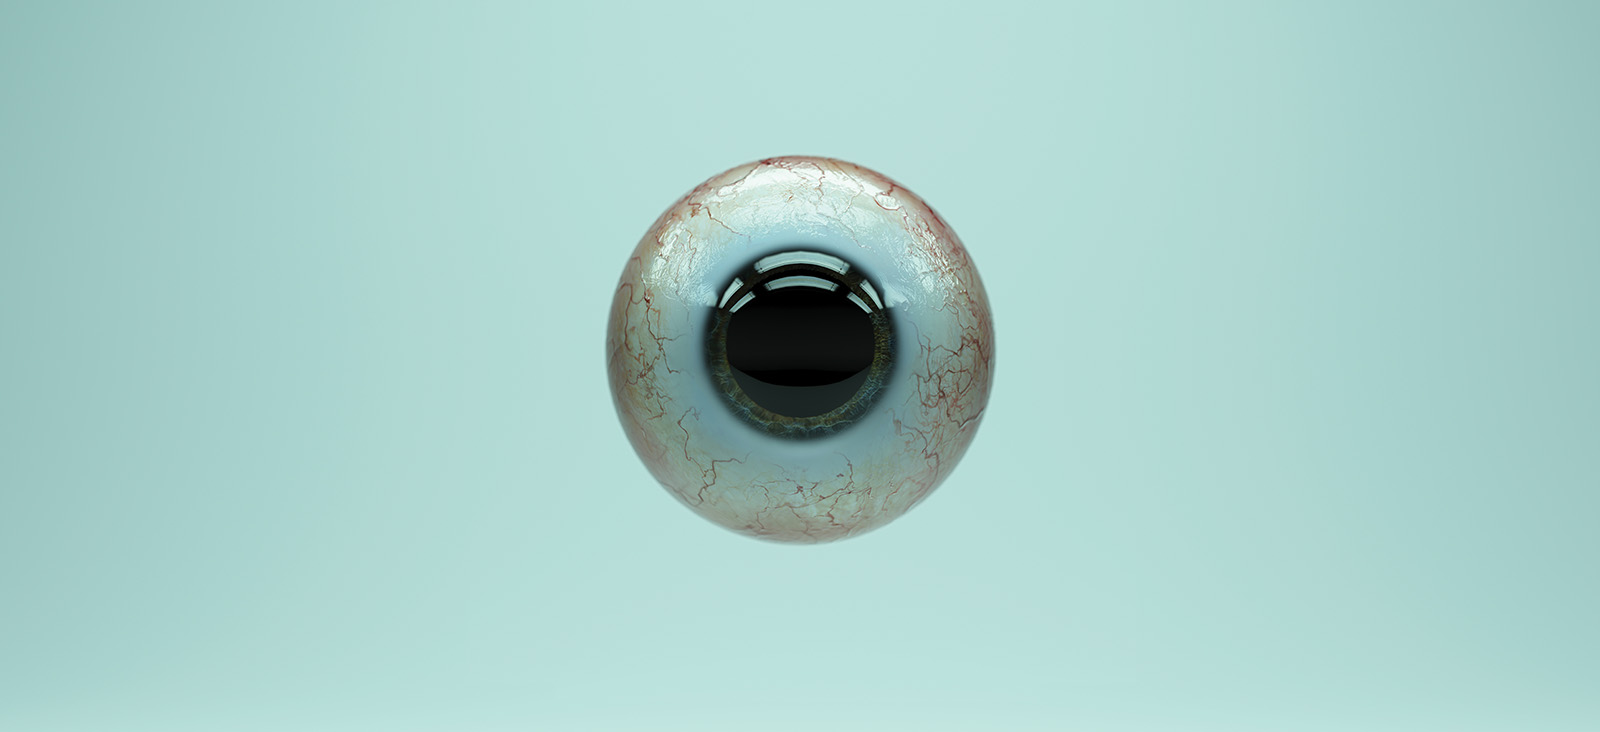

Combating Uveal Melanoma with New Treatments

Novel research, clinical initiatives aim to improve care for a rare but deadly eye cancer.

UT Southwestern Harold C. Simmons Comprehensive Cancer Center is a leader in the diagnosis and treatment of uveal melanoma, the most common primary intraocular malignancy. J. William Harbour, M.D., who was recruited to UT Southwestern as Chair and Professor of Ophthalmology in 2021, is an internationally recognized authority on uveal melanoma. His team is involved with innovative research and clinical initiatives aimed at transforming the treatment and outcomes of patients with this life-threatening malignancy.

Uveal melanoma represents approximately 5% of all melanoma diagnoses. Dr. Harbour says that patients often have questions about their diagnosis and life expectancy, which depend on a number of factors including the genetic subtype of their melanoma. Simmons Cancer Center’s unique care model facilitates seamless transition between different specialties to align with each patient’s unique treatment plan.

“Treating uveal melanoma requires a multidisciplinary approach. Treatment may include laser therapy, brachytherapy, surgery for primary disease of the eye, ongoing imaging surveillance for multiple years to monitor for distant spread to the liver or other organs, and systemic chemotherapy. It is also important to consider participation in a clinical trial to evaluate new therapies,” explains Sanjay Chandrasekaran, M.D., Assistant Professor of Internal Medicine in the Division of Hematology and Oncology at UT Southwestern.